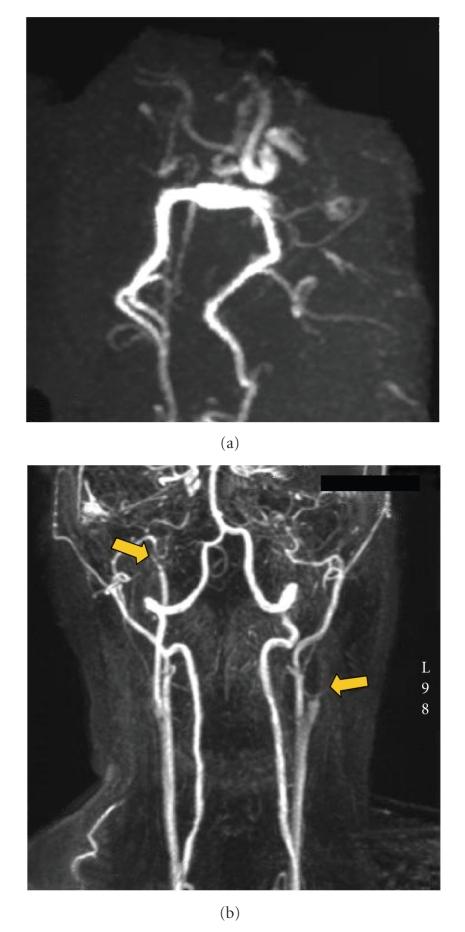

The challenge in acute stroke is still to reperfuse as early as possible the ischemic territory. Since fibrinolytic therapies have a limited window with potential risk of bleeding, having a nonpharmacologic mean to recruit vessels in area surrounding necrosis might be useful. We propose here to use antigravity suit inflated at "venous" pressure levels to shift blood towards thoracic and brain territories. We report two cases of spectacular clinical recovery after acute carotid occlusion.

急性中风的挑战仍然是尽早使缺血区域再灌注。由于纤维蛋白溶解疗法的时间窗有限且有潜在出血风险,采用一种非药物手段来促使坏死区域周围的血管恢复供血可能会有所帮助。我们在此提议使用在“静脉”压力水平充气的抗重力服,将血液转移至胸部和脑部区域。我们报告了两例急性颈动脉闭塞后临床症状显著恢复的病例。